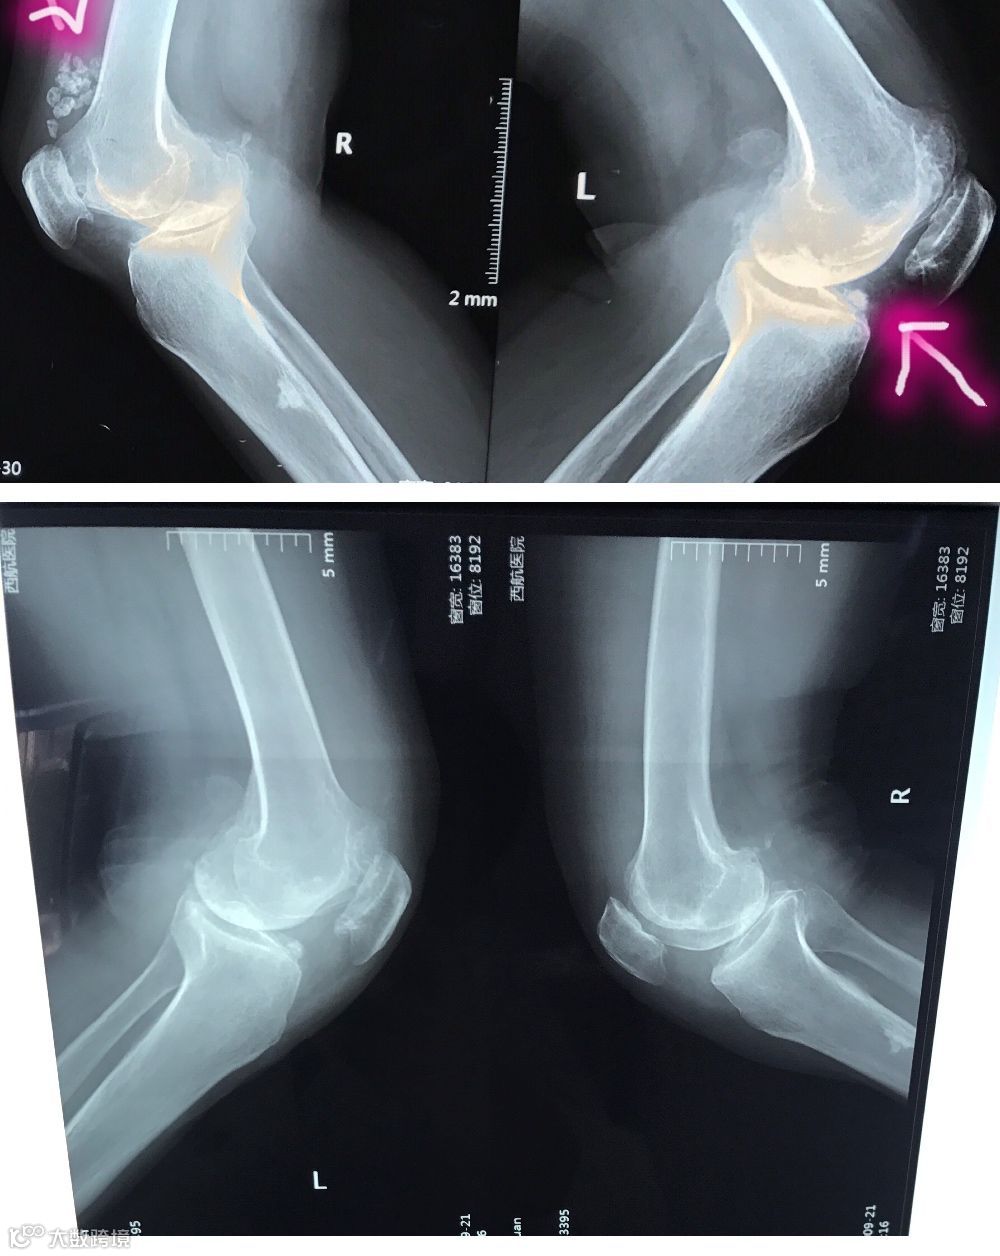

近日我院收住一名双膝骨性关节炎患者,3年前患者出现双膝关节疼痛,一直保守治疗效果不佳,影响日常生活。外二科主任倪黎明综合判定后认为患者有手术指征,在患者明确不接受关节置换情况下,向患者及家属告知可行关节镜手术治疗,此手术恢复快,创伤小,能解决患者之痛苦及顾虑。经过积极准备,在各功能科室及手麻科的紧密配合下顺利完成了这例双膝关节镜探查、清理及半月板成形术。

术前术后对比